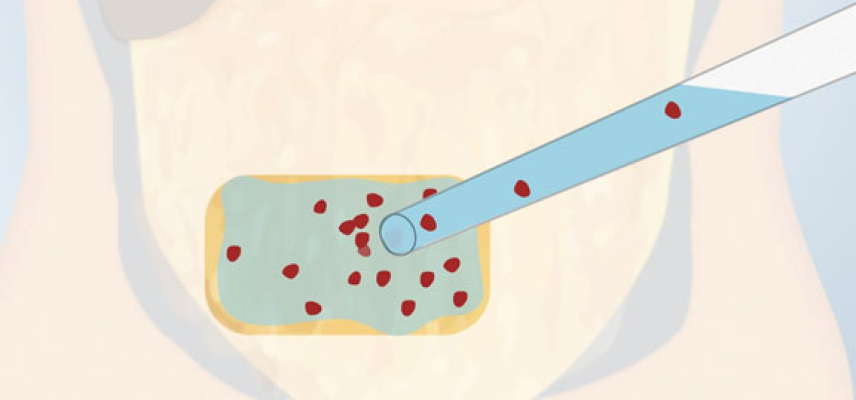

Esto será posible ubicando los islotes trasplantados en un lugar seguro, que protegerá este material genético tan valioso para todos. En el caso de Wendy el trasplante fue ubicado en el epiplón, también llamado omento. Están considerando dos materiales para crear este “mini órgano”, una esponja del tamaño de una moneda, compatible con el organismo. La otra alternativa es dentro de una vena, esta vena será atada en dos extremos para mantener los islotes aislados y la insulina sería transportada al resto del cuerpo por pequeñas arterias de la vena.

Los islotes son extraídos de las células madre, islotes de cerdos o células reprogramadas (islotes del mismo paciente). Para lograr mantener con vida y un funcionamiento correcto, el BioHub contará con células de oxígeno y otras células que ayudarán y defenderán a los islotes del sistema inmunológico de la persona. La protección del BioHub es vital ya que si el cuerpo lo ataca, los islotes sufrirían un ataque del sistema inmunológico similar al que provocó la diabetes tipo 1 inicialmente.